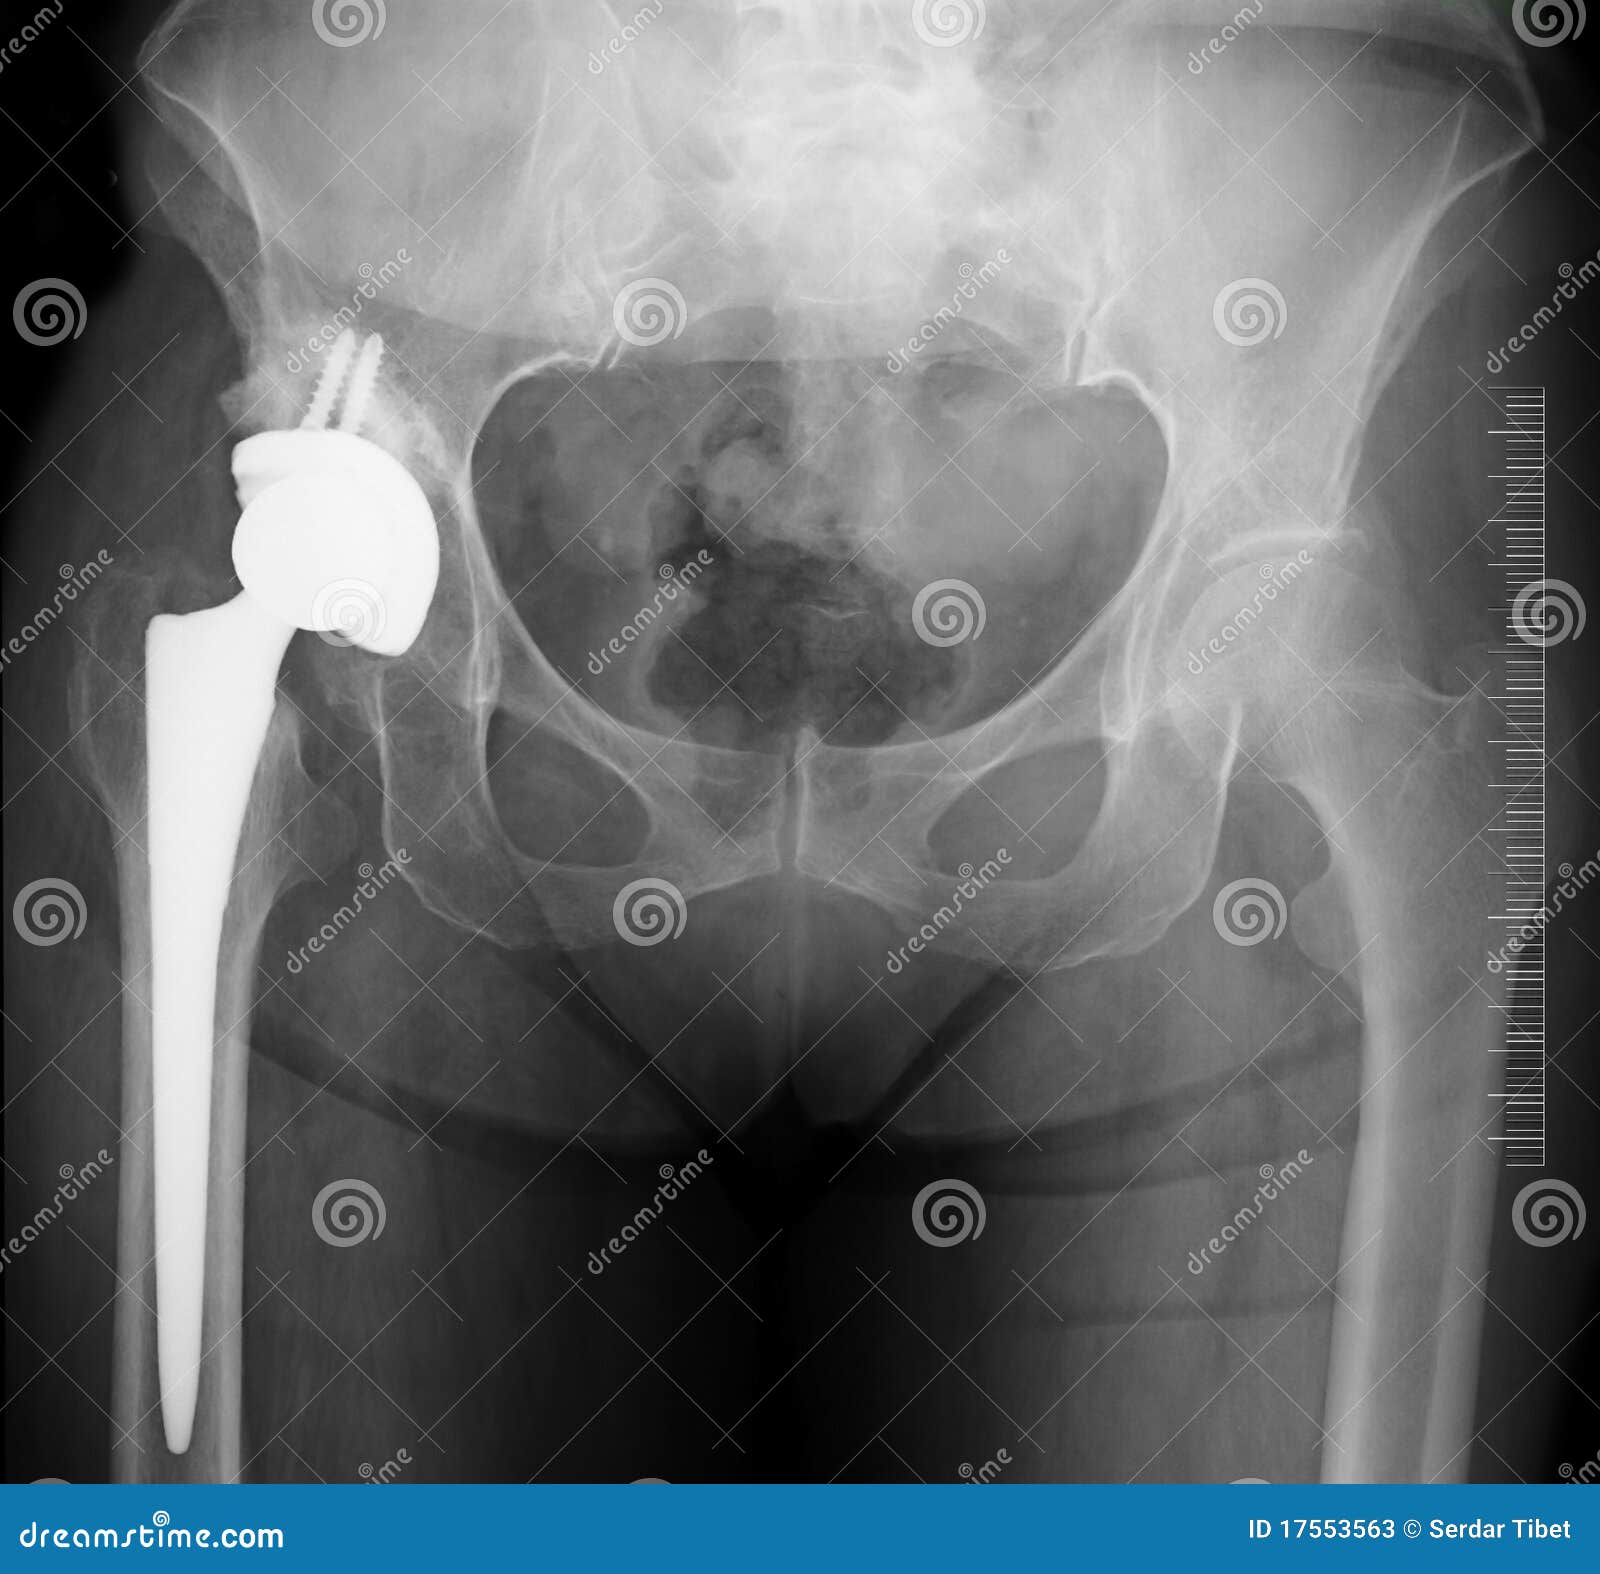

Замена таз сустава

Замена таз сустава 113 фотографий